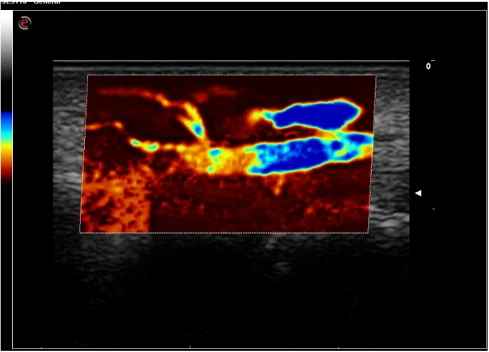

XFlow - qon elementlarini bevosita vizualizatsiya qilish rejimi

microV - mikrovaskulyarizatsiya va kapillyar qon oqimini xaritalash rejimi

Radiologiya va kardiologiyada kontrast moddalar bilan ishlashda perfuziya parametrlarini baholash uchun CUES (CnTI/LVO)

Q-Pack rang, quvvatli Doppler va CnTI texnologiyasidan foydalangan holda kontrastli perfuziya (Wi/Wo) egri chiziqlarini miqdoriy tahlil qilish uchun yangi diagnostika vositasidir.